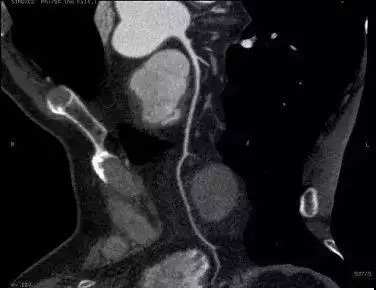

檢查結果出來,周主任看到後十分驚訝——前降支近端狹窄消失了,血管光滑了,斑塊也不見了。周主任仔細觀察各層面的影像,的確沒有發現任何斑塊。

老王現在的片子圖源:周大亮醫生